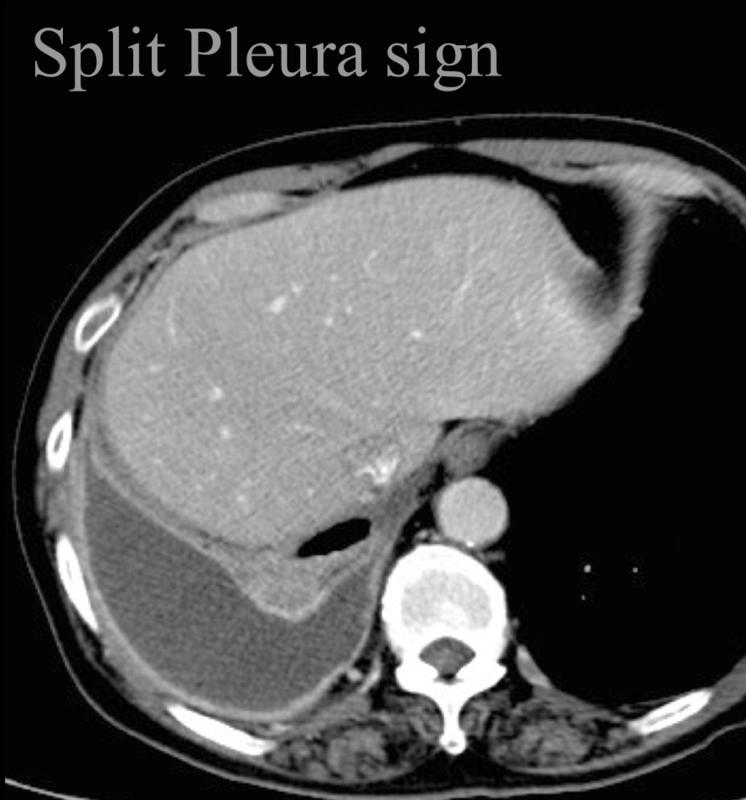

Split pleura sign

Empyema